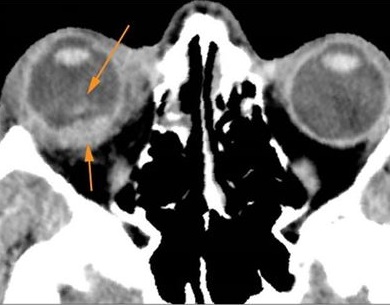

Proptosis is present. [Yes/No]

The optic nerve has a stretched appearance. [Yes/No]

The posterior aspect of the globe is tented. [Yes/No]

There is evident general optic sheath swelling or swelling at the junction of the globe and sheath to suggest an optic sheath hematoma. [Yes/No]

There is evident subretinal, subchoroidal or intravitreous hemorrhage. [Yes/No]